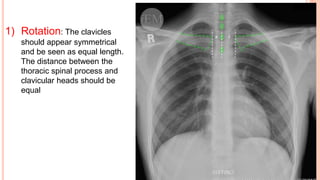

1) Rotation: The clavicles

should appear symmetrical

and be seen as equal length.

The distance between the

thoracic spinal process and

clavicular heads should be

equal

1) Rotation: Theclavicles should appear symmetrical and be seen as equal length. The distance between the thoracic spinal process and clavicular heads should be equal